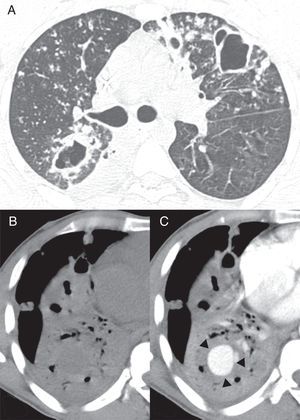

A) Imagen de tomografía computarizada (TC) axial a nivel de la bifurcación bronquial obtenida con configuración en ventana de pulmón. Muestra múltiples nódulos bilaterales y cavidades en el parénquima pulmonar. Imágenes de TC en ventana mediastinal a nivel de los lóbulos inferiores, antes (B) y después (C) de la administración de contraste muestran una consolidación en el lóbulo inferior derecho con una lesión redonda, con captación dentro del área consolidada (flechas).

Hemos leído con atención el interesante caso de un varón de 33 años con hemoptisis descrito por Peghini Gavilanes et al.1, en el cual una tomografía computarizada torácica con contraste mostró un aneurisma de Rasmussen secundario a tuberculosis. El paciente falleció 2 días después debido a una hemoptisis masiva. Aunque los aneurismas de Rasmussen con frecuencia se presentan como lesiones nodulares en lesiones tuberculosas cavitarias o adyacentes a estas1,2, también pueden aparecer en consolidaciones, lo que hace más difícil su detección. Nos gustaría informar del caso similar de un varón de 37 años, que ingresó en el servicio de urgencias con hemoptisis. El paciente tenía antecedentes de tuberculosis pulmonar (TB) tratada de forma irregular durante los 2 años anteriores y el cultivo de esputo fue positivo para bacilos ácido-alcohol resistentes. La fibrobroncoscopia mostró sangrado activo procedente del bronquio del lóbulo inferior derecho. Una tomografía torácica con contraste mostró nódulos y cavidades indicativos de tuberculosis pulmonar activa, y una consolidación en el lóbulo inferior derecho con una lesión redondeada con captación en el área consolidada (fig. 1). Se realizó una embolización transcatéter con espirales. Se pautó también tratamiento para la tuberculosis, y el paciente se recuperó bien, sin recurrencia de la hemorragia durante un año de seguimiento.